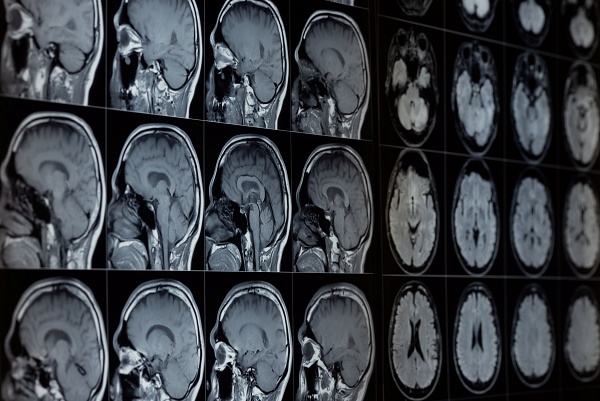

의료 AI는 암 조기 발견과 병원 업무 효율화를 위한 강력한 도구로 부상하고 있다 [사진: 셔터스톡] |

[디지털투데이 AI리포터] 중국과 미국을 중심으로 인공지능(AI)이 의료 현장에서 빠르게 활용 범위를 넓히고 있다. 암 조기 진단부터 병원 운영 효율화까지 성과가 이어지는 한편, 임상적 한계와 윤리적 우려도 동시에 제기된다.